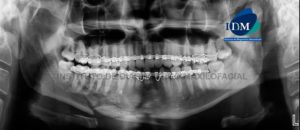

Paciente de sexo masculino 26 años de edad acude al Instituto de Diagnóstico de Maxilofacial para control post tratamiento. A la evaluación de la radiografía